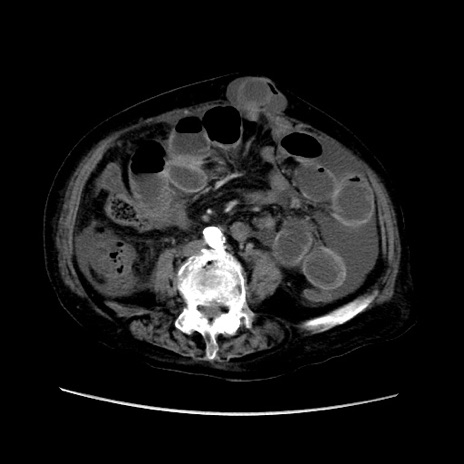

症例31(横断像)

【症例】80歳代 女性

【主訴】腹部膨満感

【現病歴】他院にて肝硬変にてフォロー中。1週間前から便秘、腹部膨満感、臍部腫瘤あり受診となる。

【既往歴】肝硬変

【身体所見】腹部膨隆あり、皮膚変化なし、疼痛なし。

【データ】WBC 4600、CRP 0.25